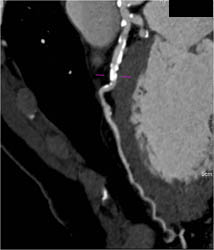

Diseased LAD